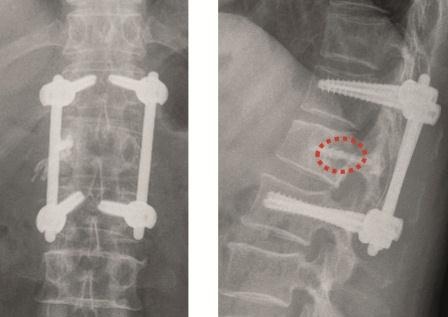

Fixateur interne: Haben die Osteolysen bereits Frakturen verursacht und weisen die betroffenen Wirbelkörper relevante Deformitäten auf, hat sich die perkutane überbrückende Stabilisierung mittels Fixateur interne bewährt (Abb. 2a und b). Der betroffene Wirbel kann ggf. additiv kyphoplastiert werden. Angesichts der sich zumeist anschließenden Radiatio verzichten wir jedoch zumeist darauf. Die Schrauben können je nach Knochenqualität zur Erhöhung der Stabilität wie üblich auch zementaugmentiert werden.